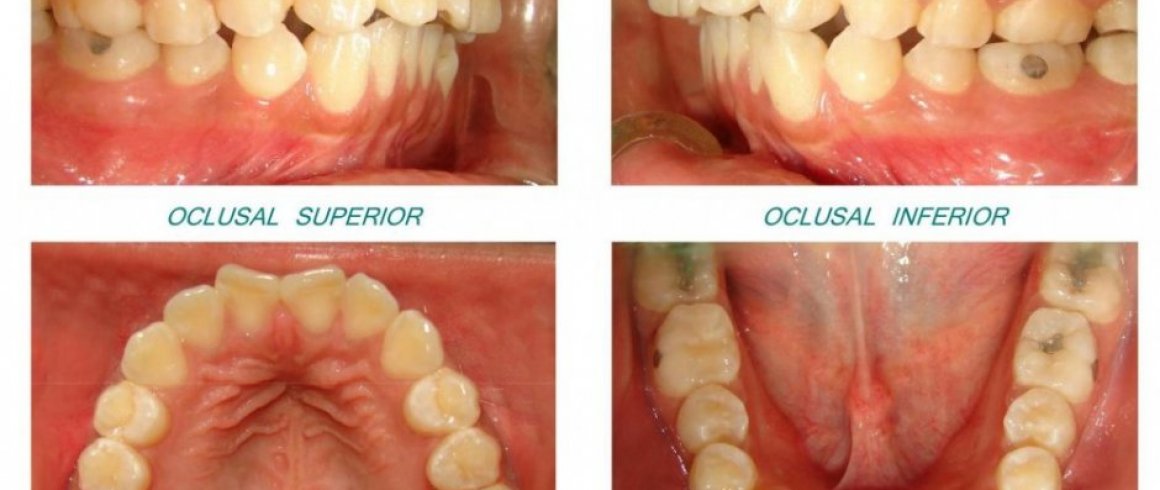

- Fotografía Digital

- Fotografías Intraorales